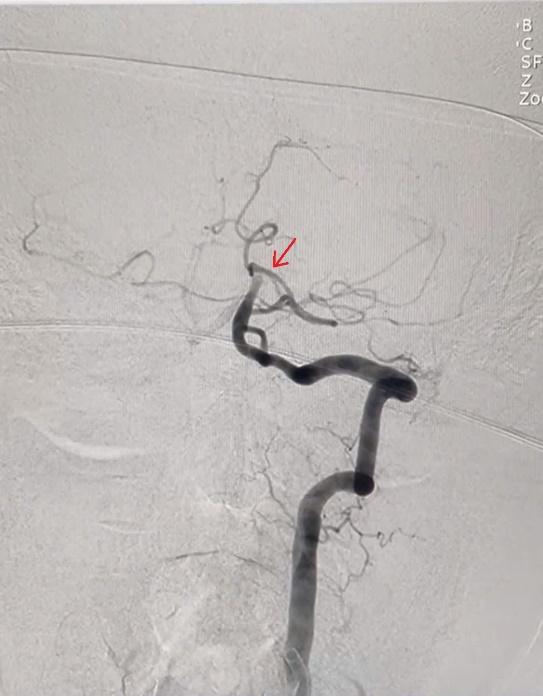

Hình DSA vị trí tắc trước can thiệp

Kết quả chụp CT não cho thấy vùng nhồi máu não bên trái bệnh nhân vẫn còn trong "giờ vàng" cấp cứu nên bác sĩ đã chỉ định tiêm thuốc tiêu sợi huyết ngay tại phòng CT. Đồng thời, trong quá trình tiêm, bệnh nhân được tiếp tục chụp CTA để đánh giá tình trạng mạch máu não. Kết quả ghi nhận có tắc mạch máu lớn – động mạch thân nền.

Ngay lập tức, bệnh nhân được chỉ định can thiệp mạch lấy huyết khối, loại bỏ cục máu đông gây tắc nghẽn mạch máu. ThS-BS Đỗ Quốc Vĩnh, Khoa Sọ não cột sống 1- Bệnh viện Đa khoa Xuyên Á (TP HCM), cho biết ca can thiệp diễn ra thành công chỉ sau 15 phút, các khối máu đông đã được lấy ra, tái thông mạch máu não thành công. Đặc biệt, đối với bệnh nhân đã có tiền sử nhồi máu cơ tim và đã đặt stent, mọi thao tác đều đòi hỏi sự chính xác cao nhằm kiểm soát các nguy cơ trong quá trình can thiệp.